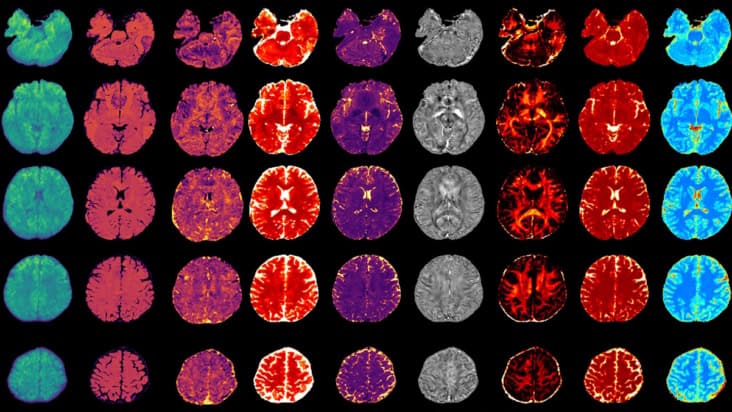

New MRI technique simultaneously maps multiple structural, physiological and molecular biomarkers to characterize brain tumours and multiple sclerosis lesions